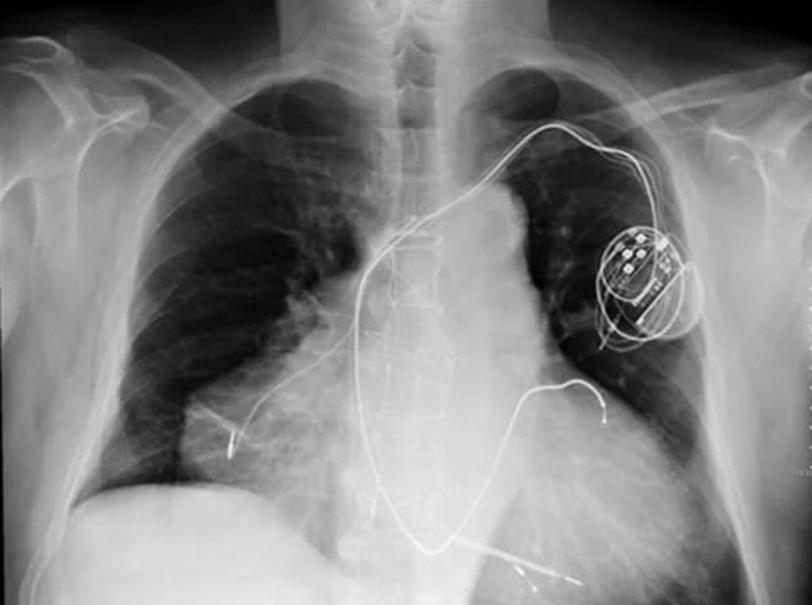

Үш жүрекпен дүниеге келген ер адамға гипертониялық трансплатация жасалған.